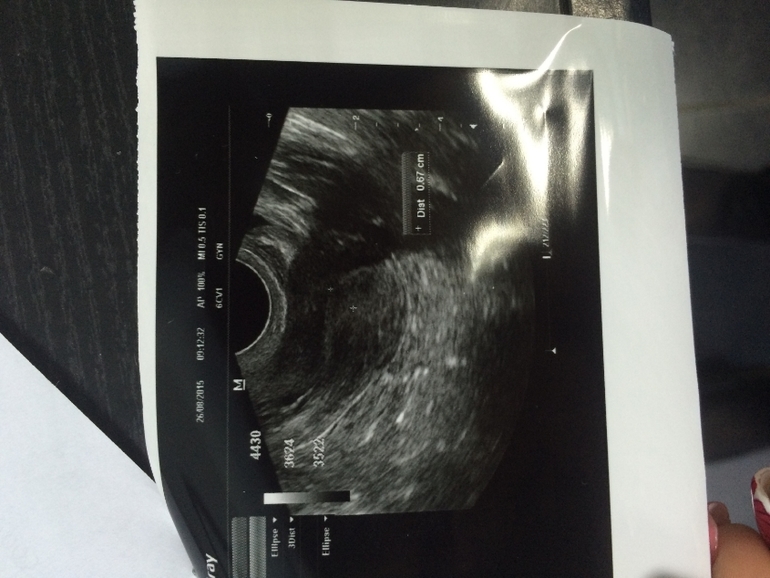

14дц узи

фолликулы от 5-9мм от 12-16штук преимущественно в корковом слое

Узи 21дц. Новый врач - новый взгляд.. Эндометриоидная киста или киста желтого тела?